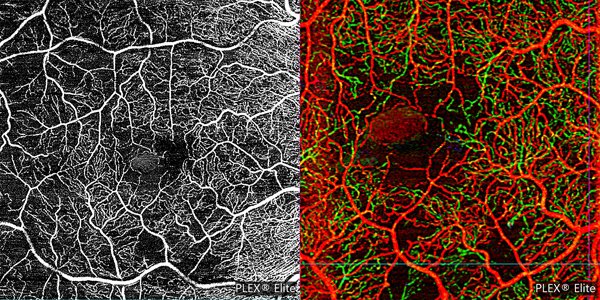

Optical coherence tomography angiography (SS-OCTA, PlexElite™, Carl Zeiss Meditec) en face revealed star-shaped flow signals in the avascular outer retinal slab. Signal patterns were identical to those associated with the accumulations seen in structural en face OCT. These areas of hyperreflective intreretinal fluid (IRF) tend to localize around the foveal avascular zone (FAZ) and within the deep retinal plexus. SSPiM always is presented at the edge or border of a vascular plexus at a vascular-avascular junction (Fig. 2).

Figura 2. On eye right the OCTA (A) 6 mm x 6 mm and (B) 3 mm × 3 mm depth-encoded color showed the SSPiM on the en face image corresponding to the hyperreflective fluid begins at the border of the FAZ and extends peripherally. On depth-encoded images red corresponds to the superficial retinal layer, and green to the deep retinal layer.